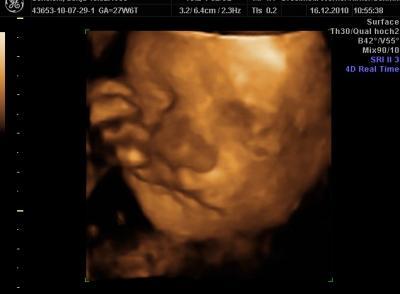

Hallo Ihr Lieben! Möchte euch heut mal meinen kleinen Schatz vorstellen! Das Bild ist von der 28. ssw Wünsche euch allen einen schönen Sonntag! Liebe Grüße

Bild zu Möchte jemand vorstellen! - Forum für März - Mamis